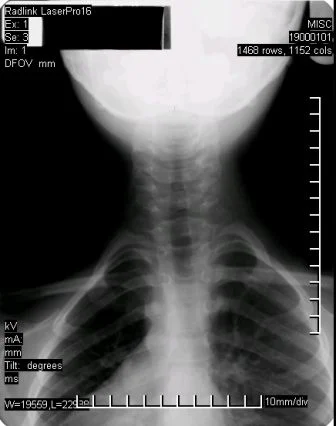

Before Corrective Care (manual short term adjusting)